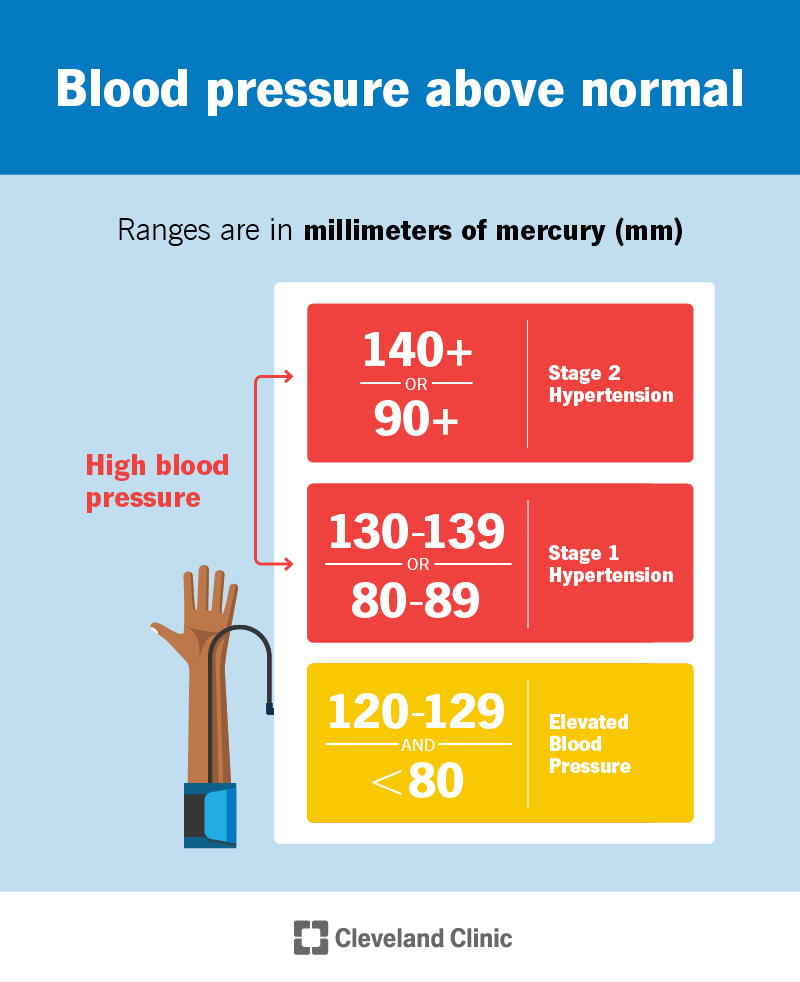

https://my.clevelandclinic.org/-/scassets/images/org/health/articles/4314-high-blood-pressure.ashx

What To Know About High Blood Pressure As You Age National Institute